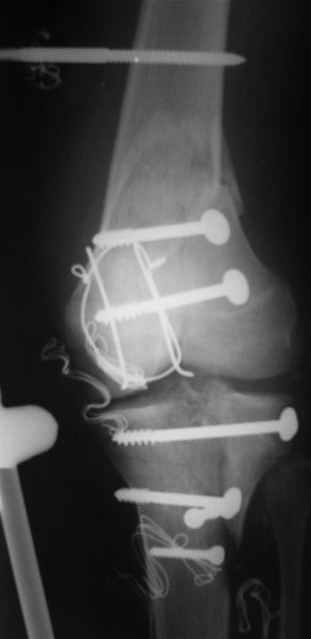

Вид раны на сегодня...

4 cутки после травмы.